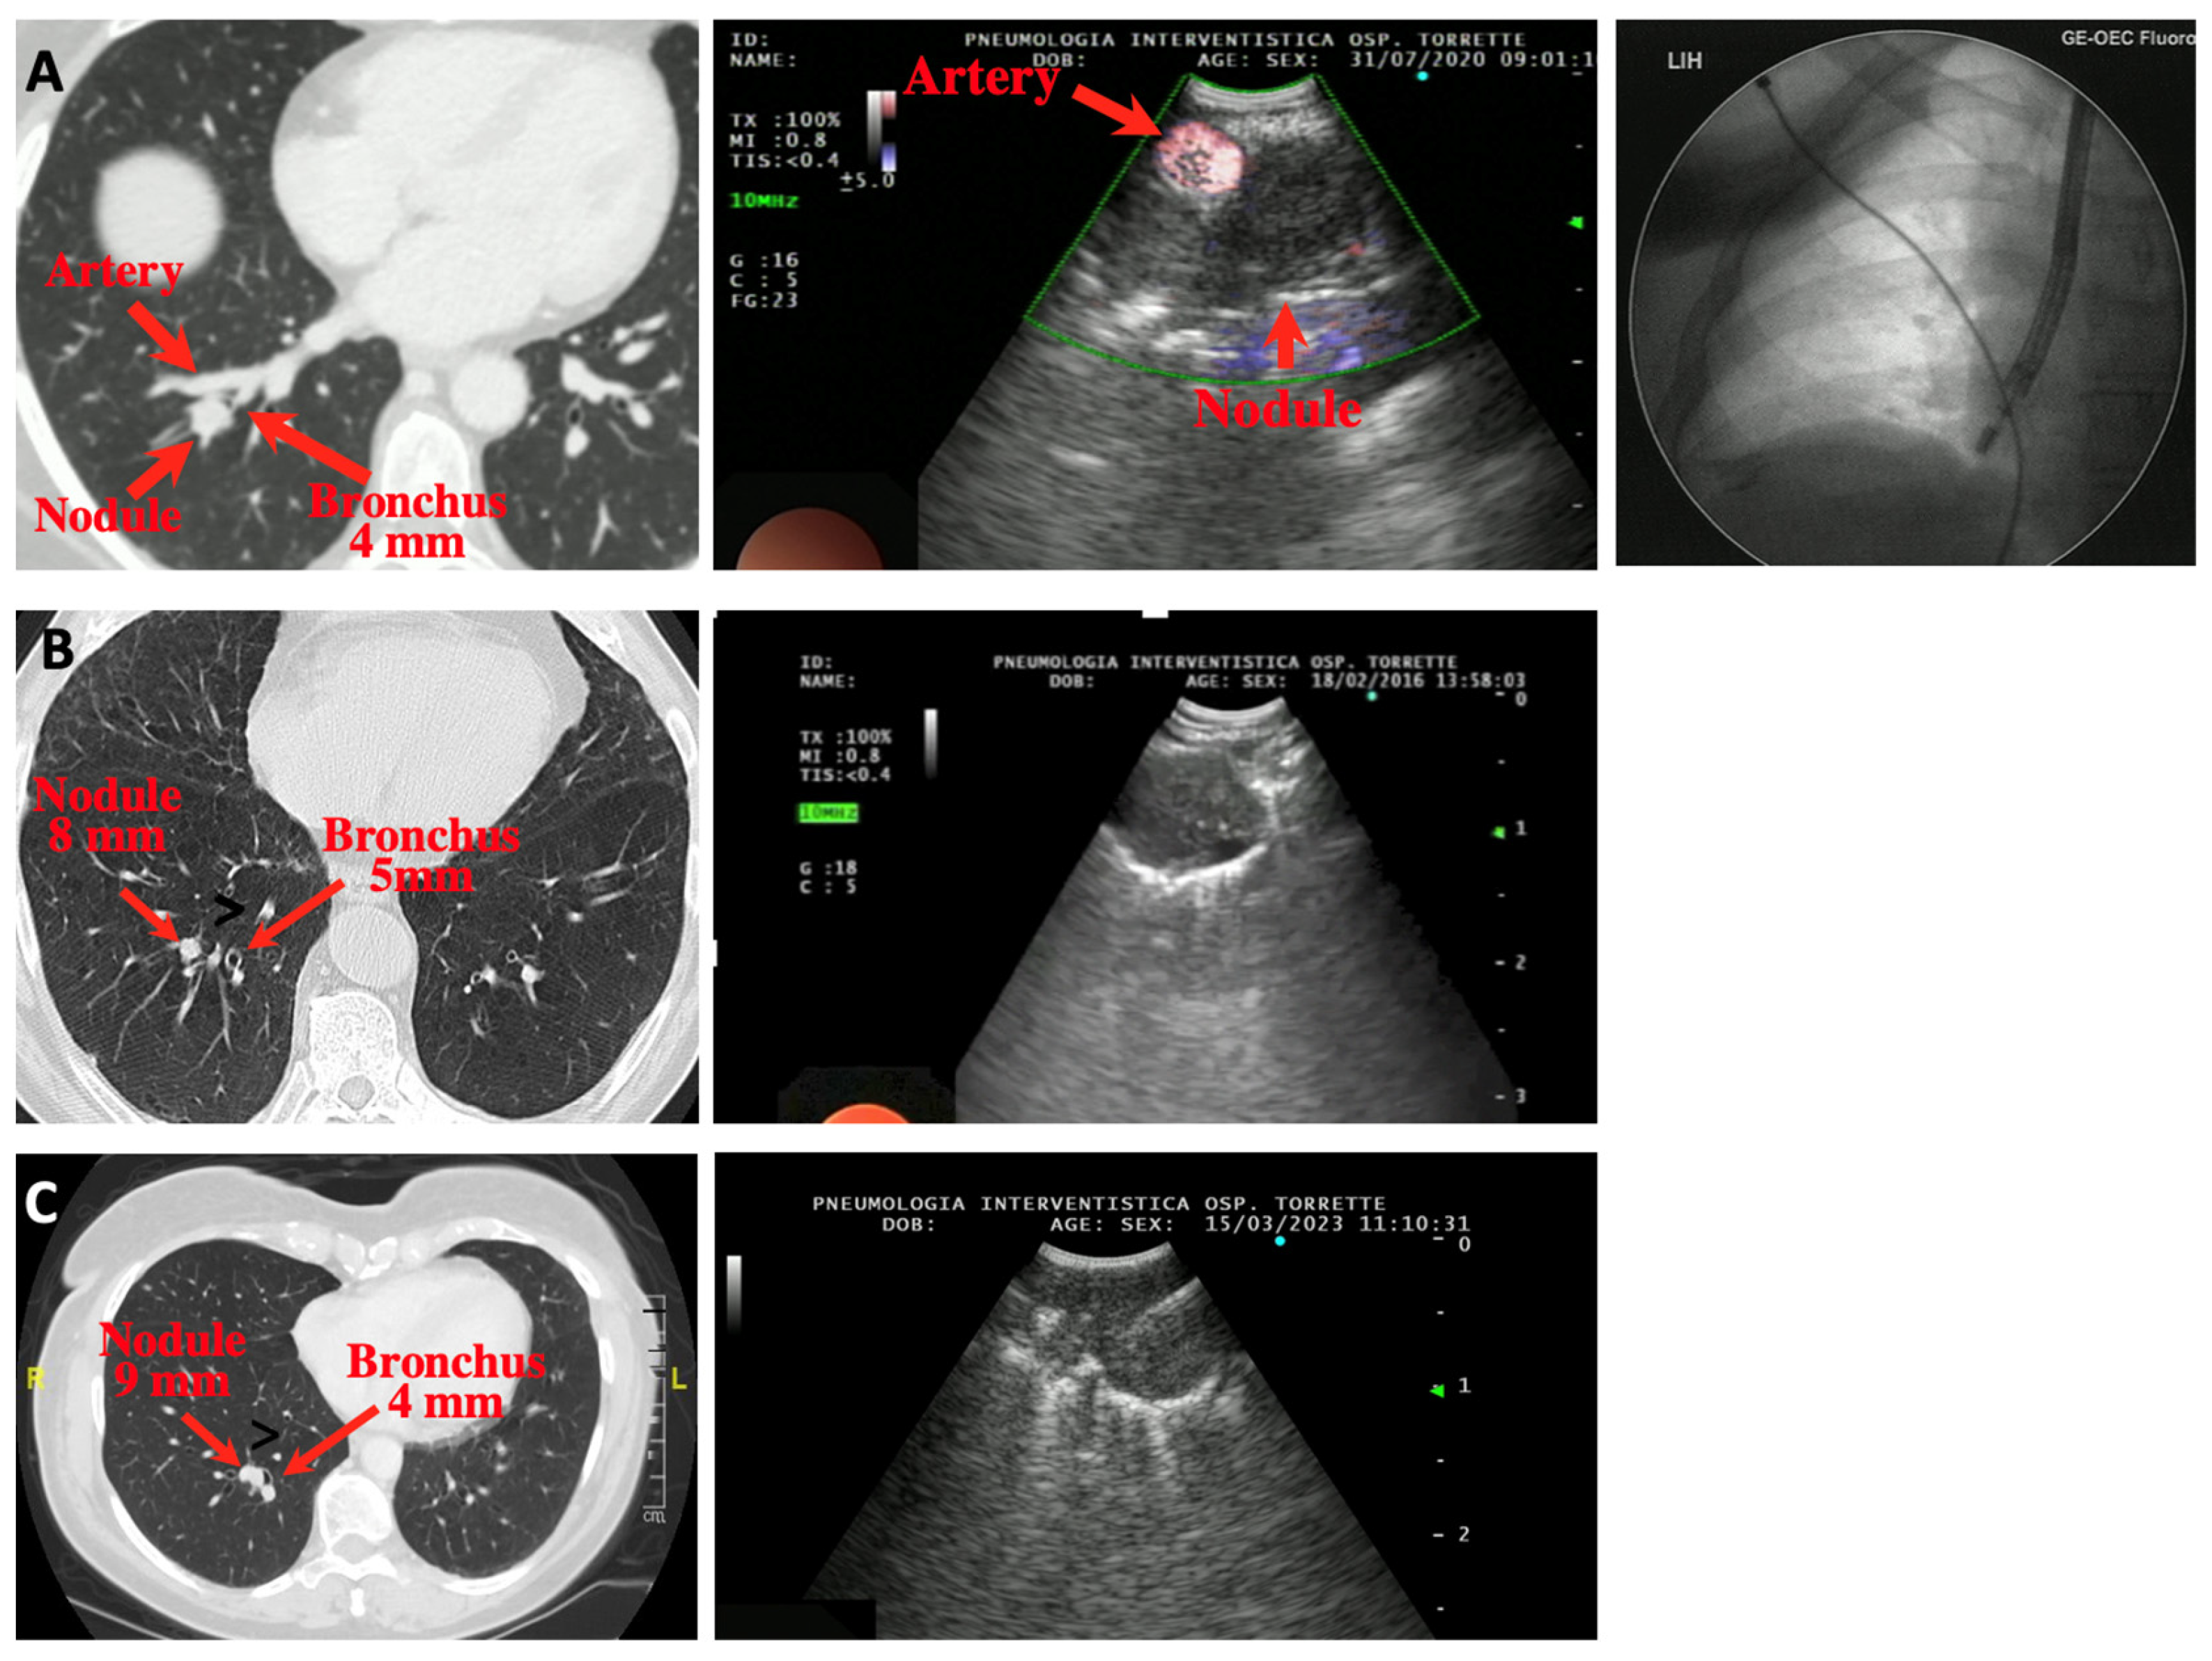

Figure 1 and Figure 2 show the CT findings and the paired ultrasonographic appearance of the pulmonary nodule in some of the patients included in the present series.

Figure 2.

Three cases of peripheral pulmonary nodules of the right lung approached using EBUS-TBNA. (A) Paired CT, ultrasound and fluoroscopic images of a case of adenocarcinoma of the posterior segment of the left right lower lobe. In the ultrasound image, a large branch of the pulmonary artery lying very close to the nodule is shown using the Power Doppler function. (B) A small nodule (8 mm) of the posterior segment of the right lower lobe (metastasis of urothelial cancer). The nodule was successfully sampled, despite a 1 cm distance from the closest bronchus, by bending and thrusting the tip of the scope towards the nodule. (C) A small nodule (9 mm) of the posterior segment of the right lower lobe (carcinoid tumor). In the ultrasound image, the needle inside the lesion is visible.

In our series, only nodules ≤ 3 cm were included, but EBUS-TBNA can obviously be used for larger lesions located in the lung periphery. Interestingly, the lesion size did not influence the likelihood of obtaining the final diagnosis in our series, a result suggesting that once the lesion is visualized ultrasonographically, the chances of retrieving diagnostic tissue is independent of its size. Indeed, we could visualize and sample even 8 or 9 mm nodules (cases B and C of Figure 2), which were finally diagnosed first as a pulmonary metastasis of urothelial cell cancer and second as a carcinoid tumor. We hypothesize that the reason for the failure to visualize the nodule in the two cases in whom this happened was related to a tributary bronchus too angled to allow for the insertion and progression of the tip of the scope.

Another limitation to the successful use of EBUS-TBNA in diagnosing PPNs is the need for a bronchus ≥ 3 mm adjacent to the lesion, although this airway does not need to be in close contact with the nodule. Indeed, in our experience (as reported in case B of Figure 2) a distance of up to 1 cm can be markedly shortened, if not completely eliminated, by bending the tip of the scope towards the lesion, a maneuver that usually brings the ultrasound probe in contact or very close to the nodule.